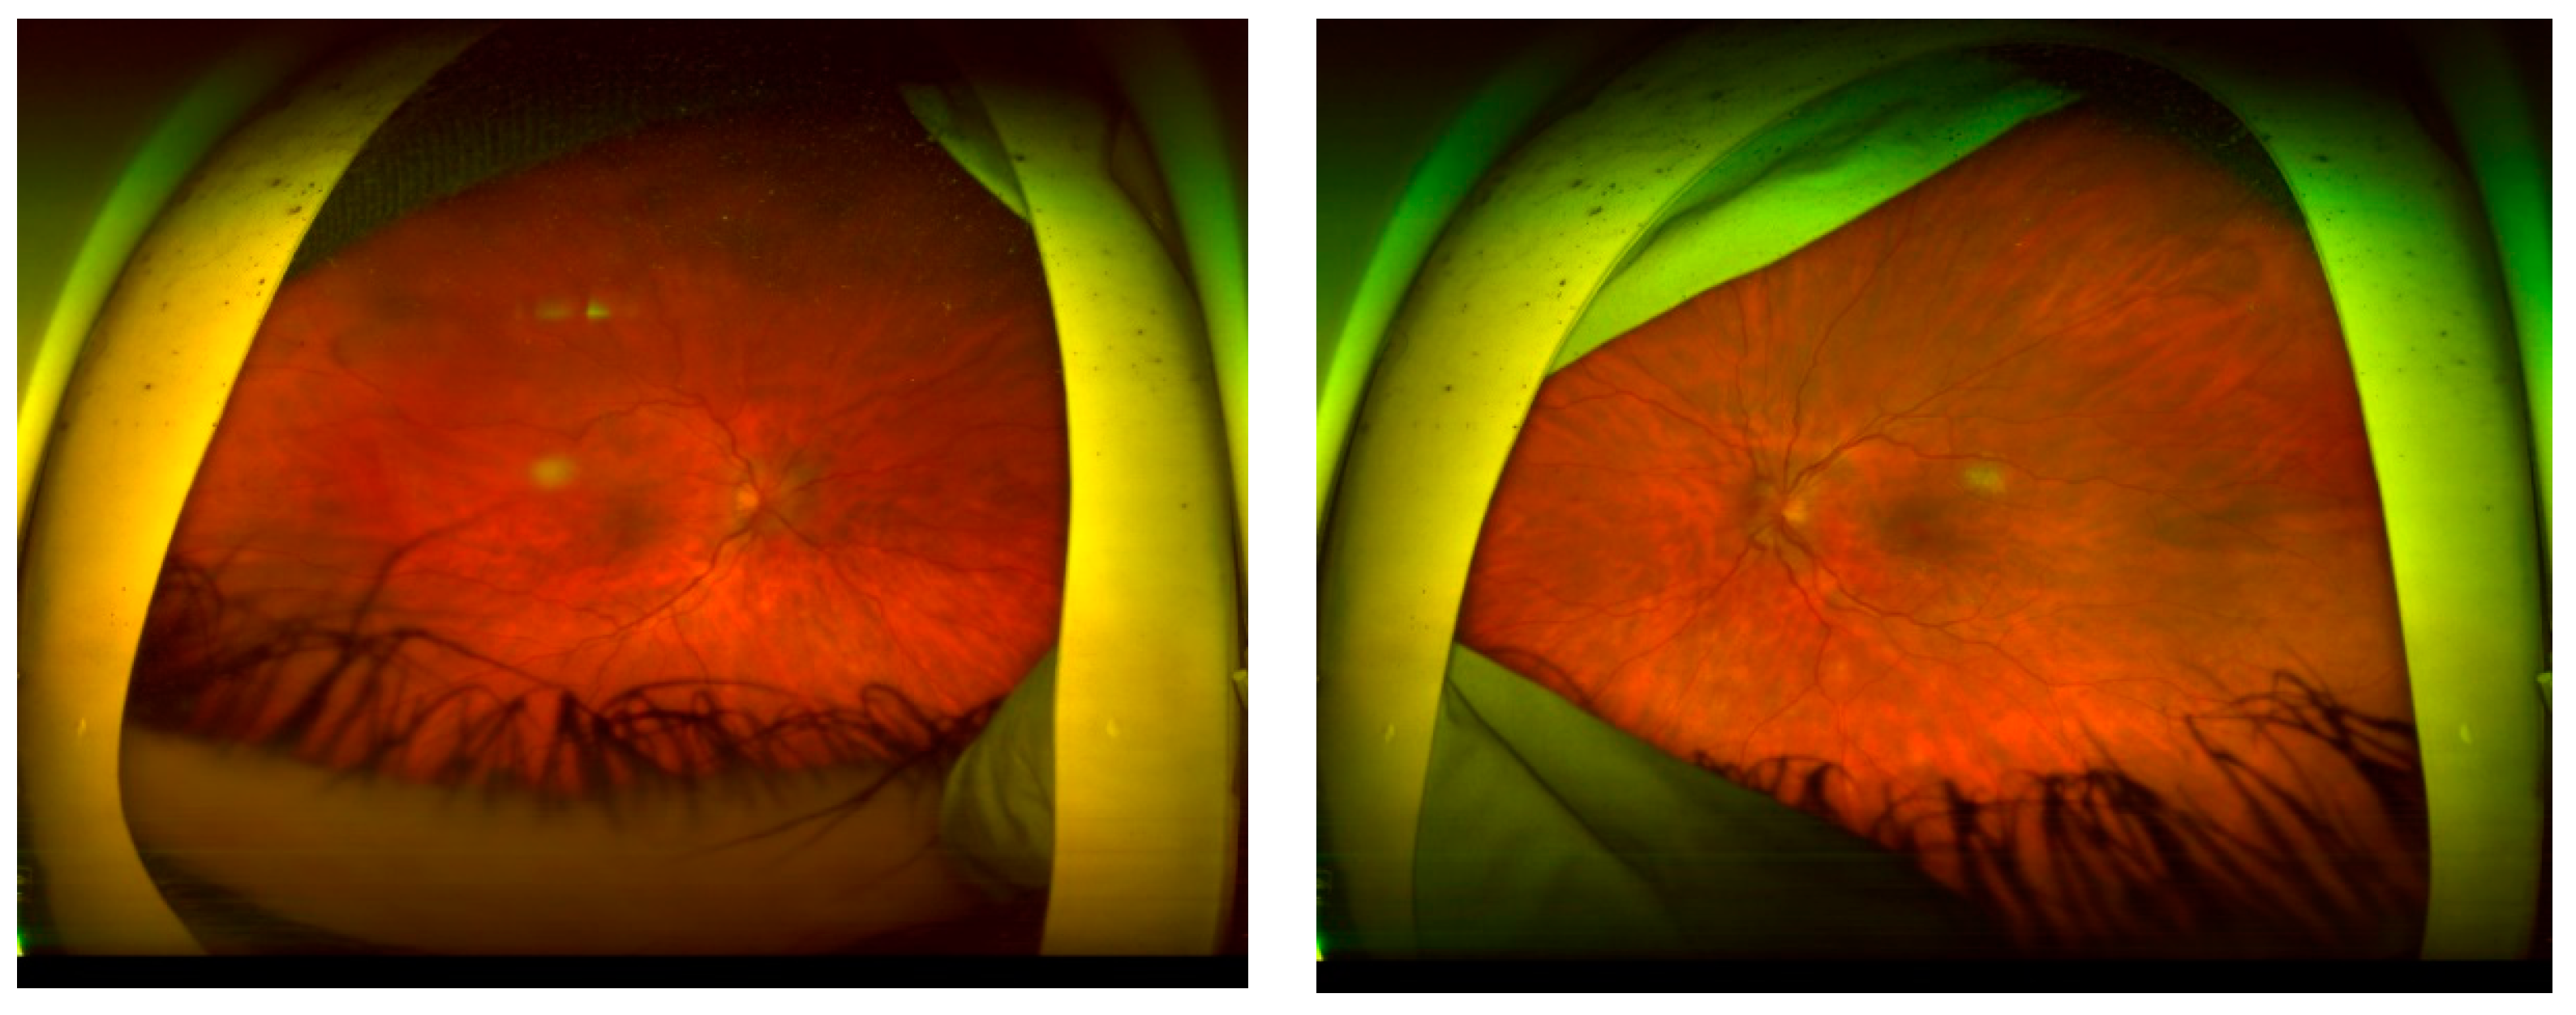

CASE DESCRIPTION